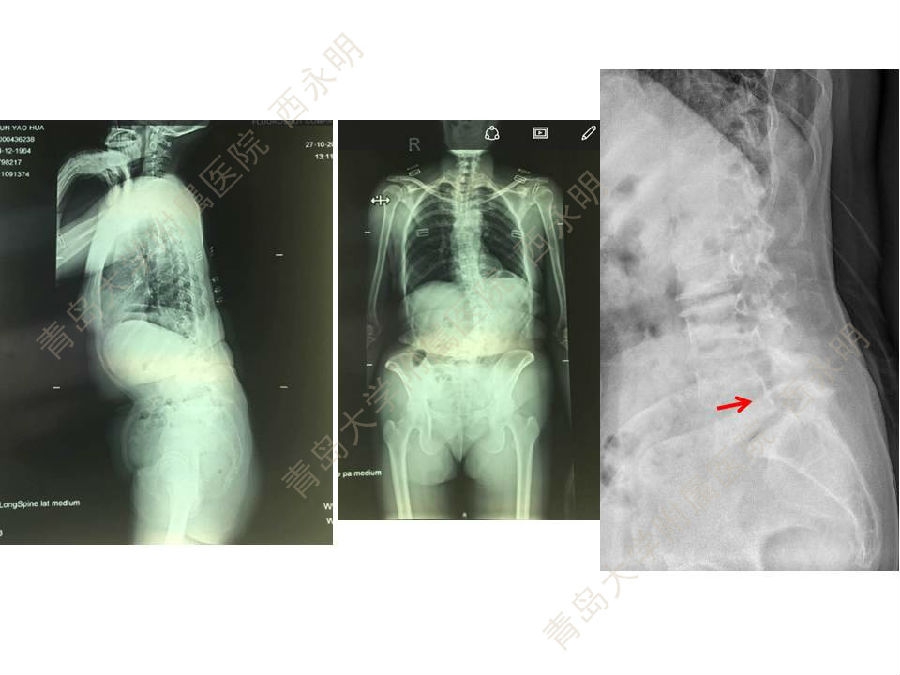

皮质骨螺钉技术及临床应用

颈椎伤病、脊柱畸形和脊柱肿瘤以及颈胸腰椎退变性疾病的微创治疗。长期从事临床一线的医、教、研工作,在多年的临床实践中积累了丰富的经验,并形成了以脊柱外科为专业方向,以颈椎外科、脊柱畸形和脊柱肿瘤为专业特色。